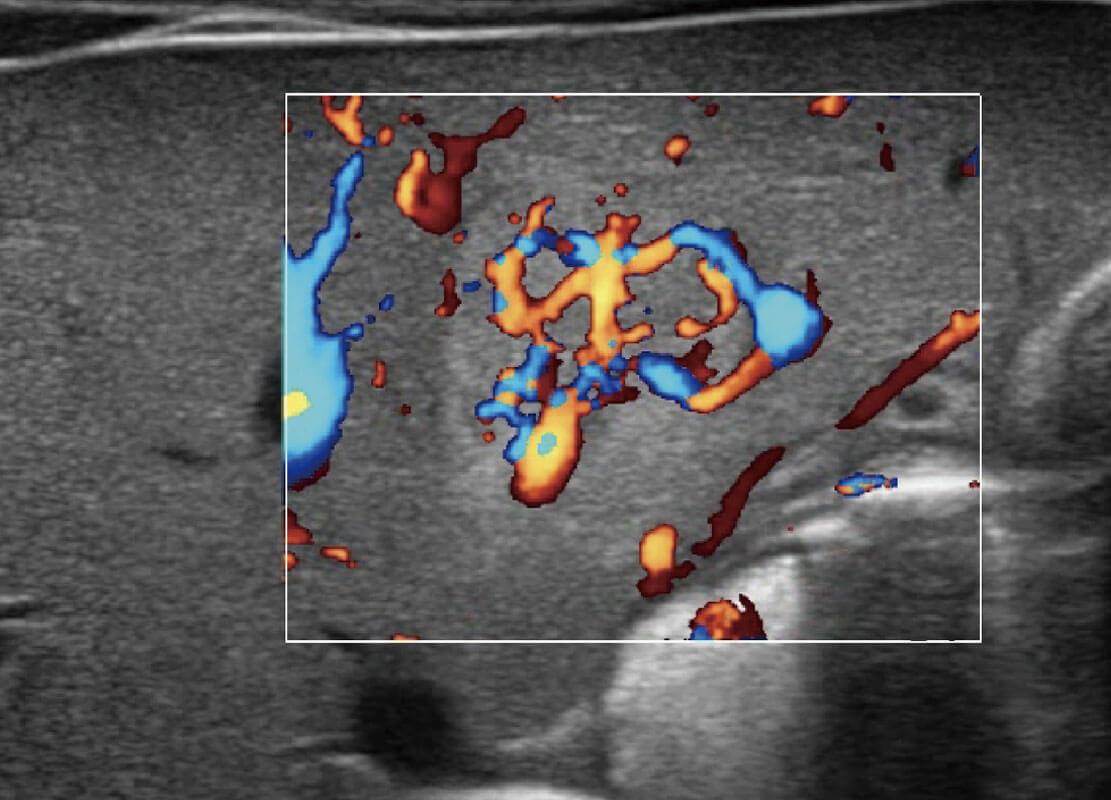

P60优异的图像质量搭载专科探头,在妇科基础疾病的诊断、卵泡生长的监测、输卵管通畅情况的判别等方面为您提供生殖应用方案。

腔内妇科-宫腔分离

腔内妇科-卵巢